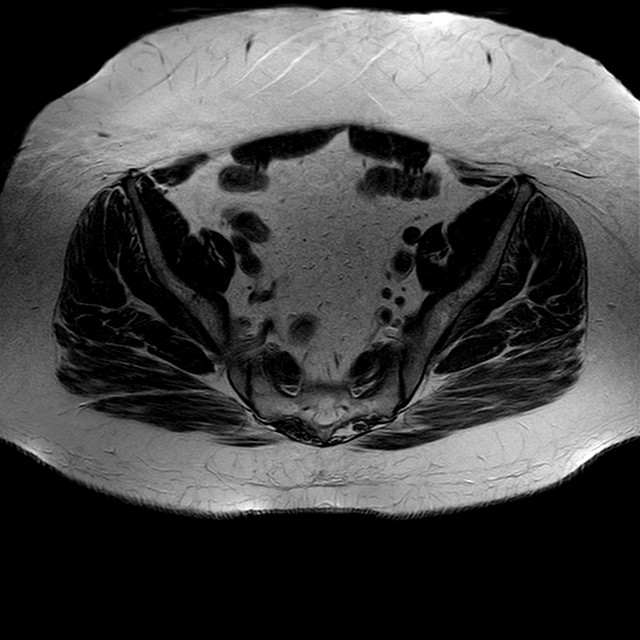

Esami: RMN BACINO

eT2w TSE

Evidenti e simmetriche alterazioni osteofitosiche in regione coxo femorale con riduzione delle rime articolari. Degenerazione completa del cercine glenoideo. Non attuali segni di versamento articolare. Non segni di edema osseo che escludono attuale algodistrofia od osteonecrosi. Lieve e simmetrica riduzione del trofismo della muscolatura glutea.